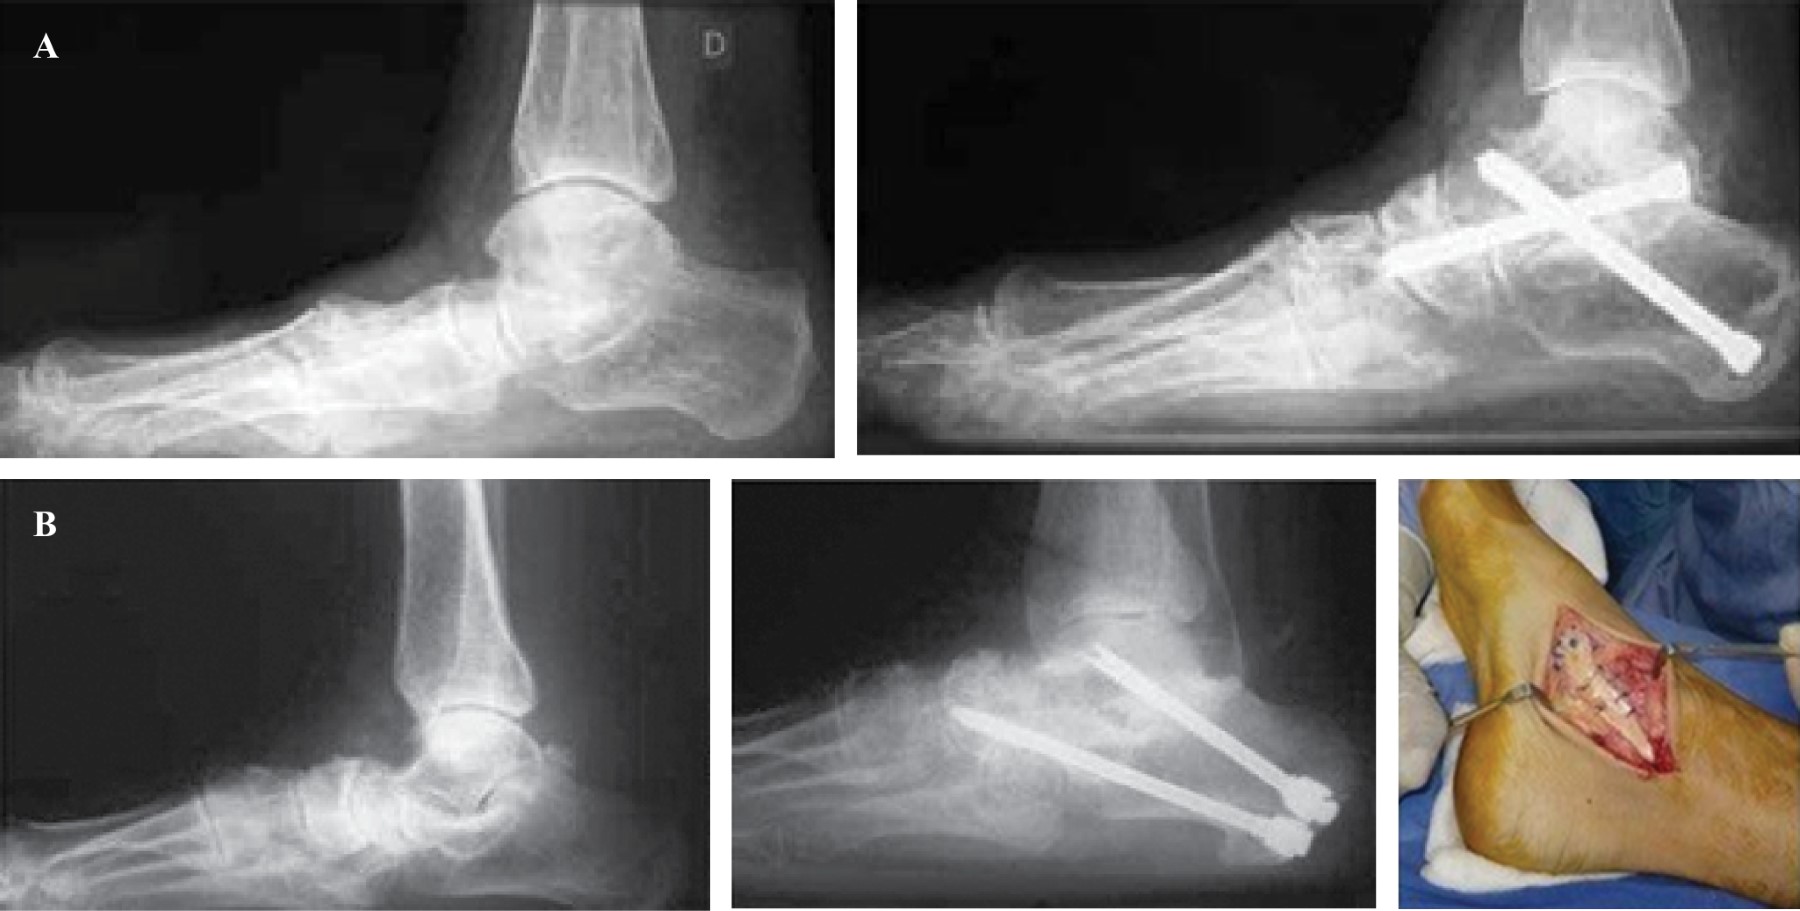

Figure 1

Figure 2

Figure 3

Figure 4

Figure 5

Figure 6

Figure 7

Figure 8

Figure 9

Figure 10

Figure 11